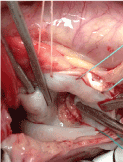

These findings conditional are not able to perform a mitral valve plasty and opt for a change with aortic mechanical prosthesis placed in the mitral position given the cardiac size do meter fitting a ring on aortic -× 21 mm and decided to place an aortic valve mitral invested in position (Figures 2-5).

Figure 4. Mitral replacement.

Figure 5. Mitral replacement with aortic mechanical valve.

Good size valve is allowed to avoid reoperation for valve replacement in the short term for placement was in supra- annular position and it was necessary to polish the myocardium to allow proper latch discs.